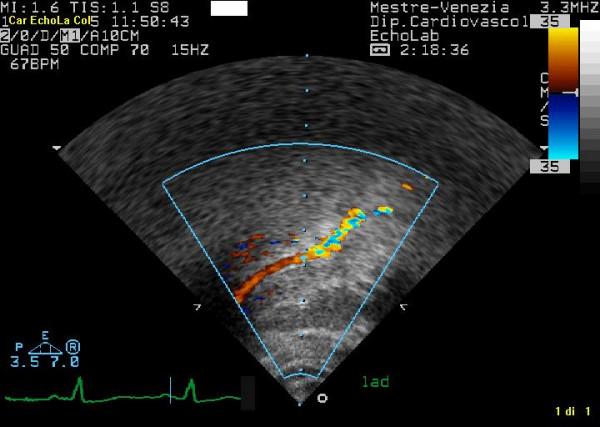

The aim of this paper is to highlight coronary investigation by transthoracic Doppler evaluation. This application has recently been introduced into clinical practice and has received enthusiastic feedback in terms of coronary flow reserve evaluation on left anterior coronary artery disease diagnosis. Such diagnosis represents the most important clinical application but has in itself some limitations regarding anatomical and technological knowledge. The purpose of this paper is to offer a didactic approach on how to investigate the different segments of left anterior and posterior descending coronary arteries by transthoracic ultrasound using different anatomical key structures as markers. We will conclude by underlining that, nowadays, innovative technology allows complete evaluation of both major coronary arteries in many patients in a resting condition as well as during pharmacology stress-tests, but we often do not know it.